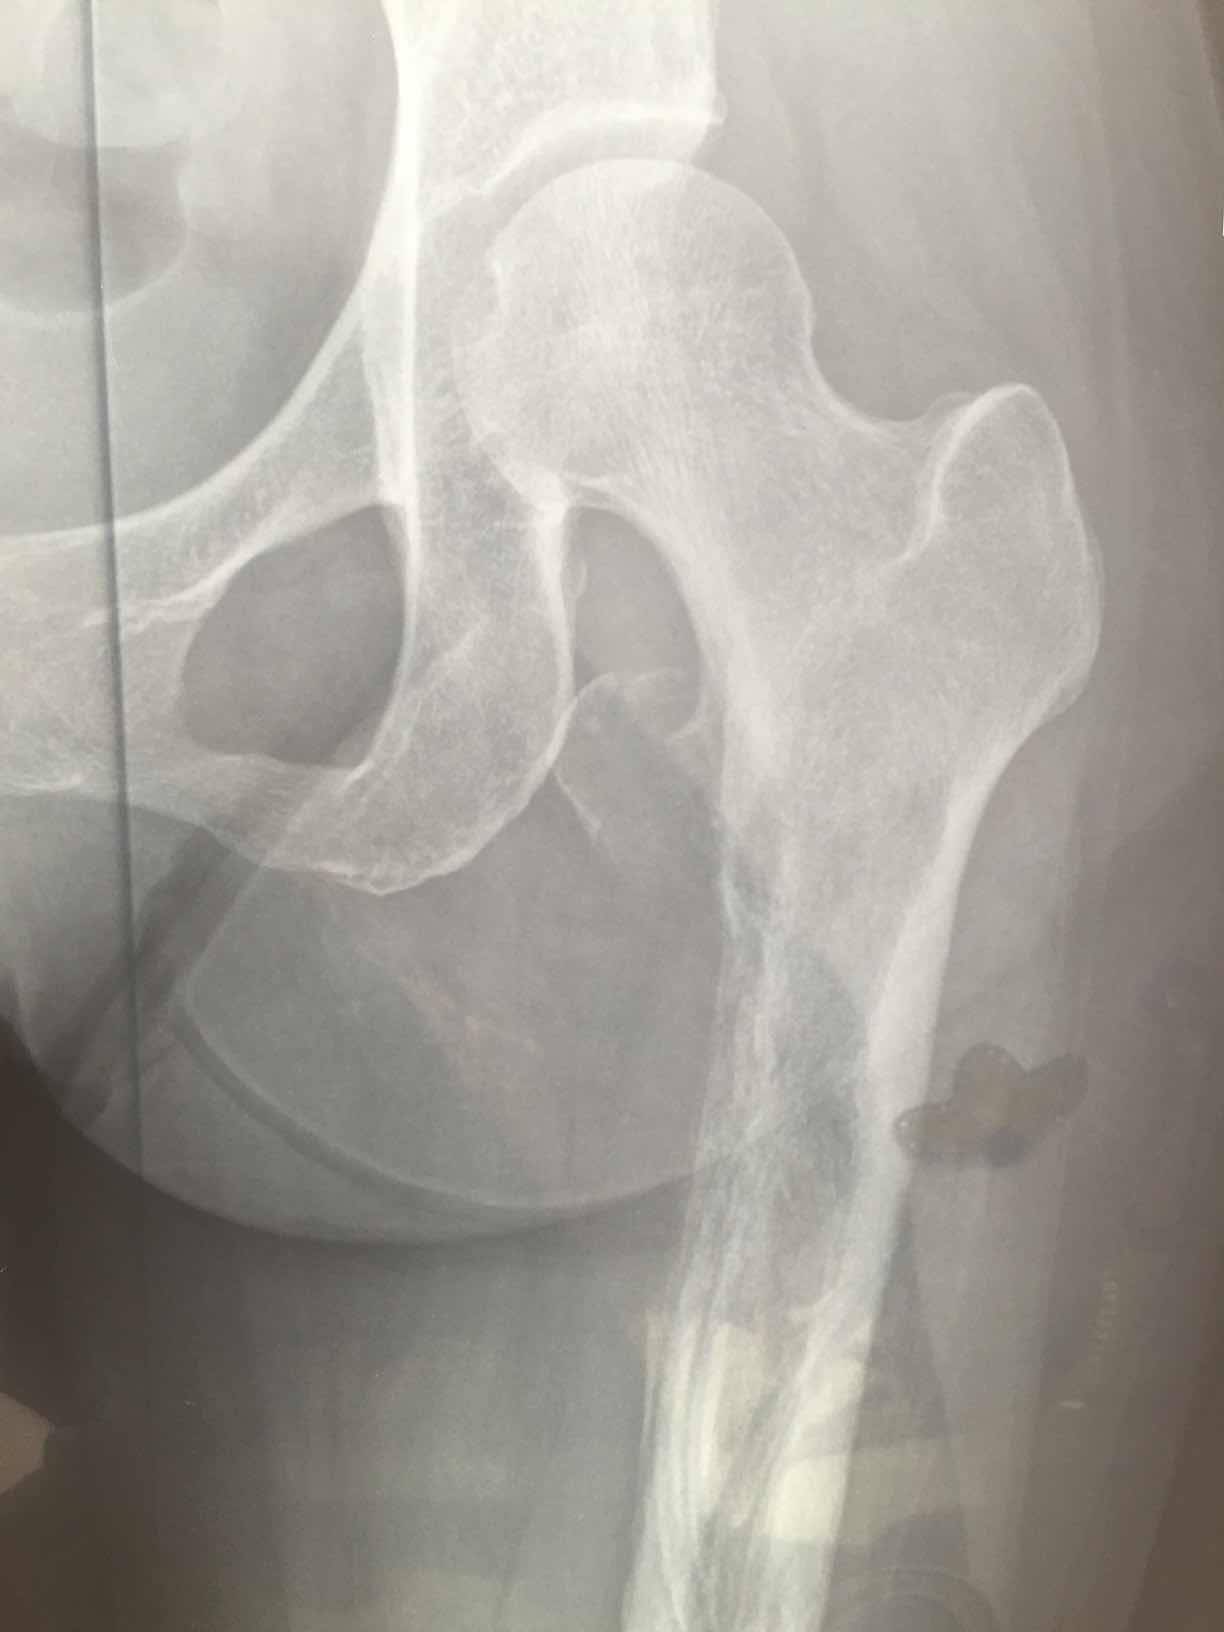

妈妈肺腺癌晚期骨转严重大腿根骨裂求大家帮忙

妈妈年前左大腿总疼,去医院检查说是腰间盘突出,在家卧床躺了3个月,前两个月还好,后一个月疼痛难忍。再去检查才发现是肺癌转移,然后主要转移到腿部比较严重,大腿根在不知情的情况下还掰了一下,造成了骨裂。去医院检查,骨科医院说是腿能做手术,但是还是建议先控制肿瘤,去了肿瘤医院,肿瘤医院说是腿没办法治疗了,因为妈妈大腿掰了一下已经目前卧床影响行走了,1月4号确诊,半月后开始打了骨转针,和吃了靶向药易瑞沙,我家是19突变,在这之前腿疼痛难忍,吃了易瑞沙就不疼了,但是还是由于大腿根骨裂影响行走,目前妈妈食欲还不错,睡眠也还好,就是躺着总说很累,求大家帮帮我,有懂ct这方面的也可以帮我看看,妈妈的腿能不能自愈,毕竟没有骨折。钙片骨转针一直在吃。求求大家帮帮忙。